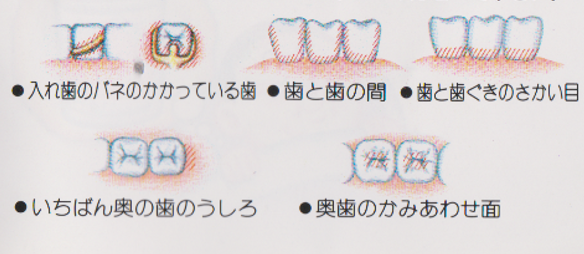

⑥ 前回詰めた綿花の状態を確認して、良い状態なら、「根管充填剤」(マスターポイント・アクセサリーポイント)というお薬を、余分な空間がないように根っこに詰めます。

⑥ 前回詰めた綿花の状態を確認して、良い状態なら、「根管充填剤」(マスターポイント・アクセサリーポイント)というお薬を、余分な空間がないように根っこに詰めます。 Q1.痛みはありますか?

Q1.痛みはありますか? ② 次に、「根管長測定器」という機械を使い、根っこの長さを正確に測ります。

② 次に、「根管長測定器」という機械を使い、根っこの長さを正確に測ります。

⑤ 次に、仮詰めをします。

⑤ 次に、仮詰めをします。 虫歯が神経まで達して炎症を起こしているので、人によってはズキズキとした痛みを感じる方もいます(>_<)

虫歯が神経まで達して炎症を起こしているので、人によってはズキズキとした痛みを感じる方もいます(>_<)